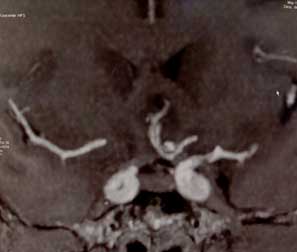

IRM tractografía.